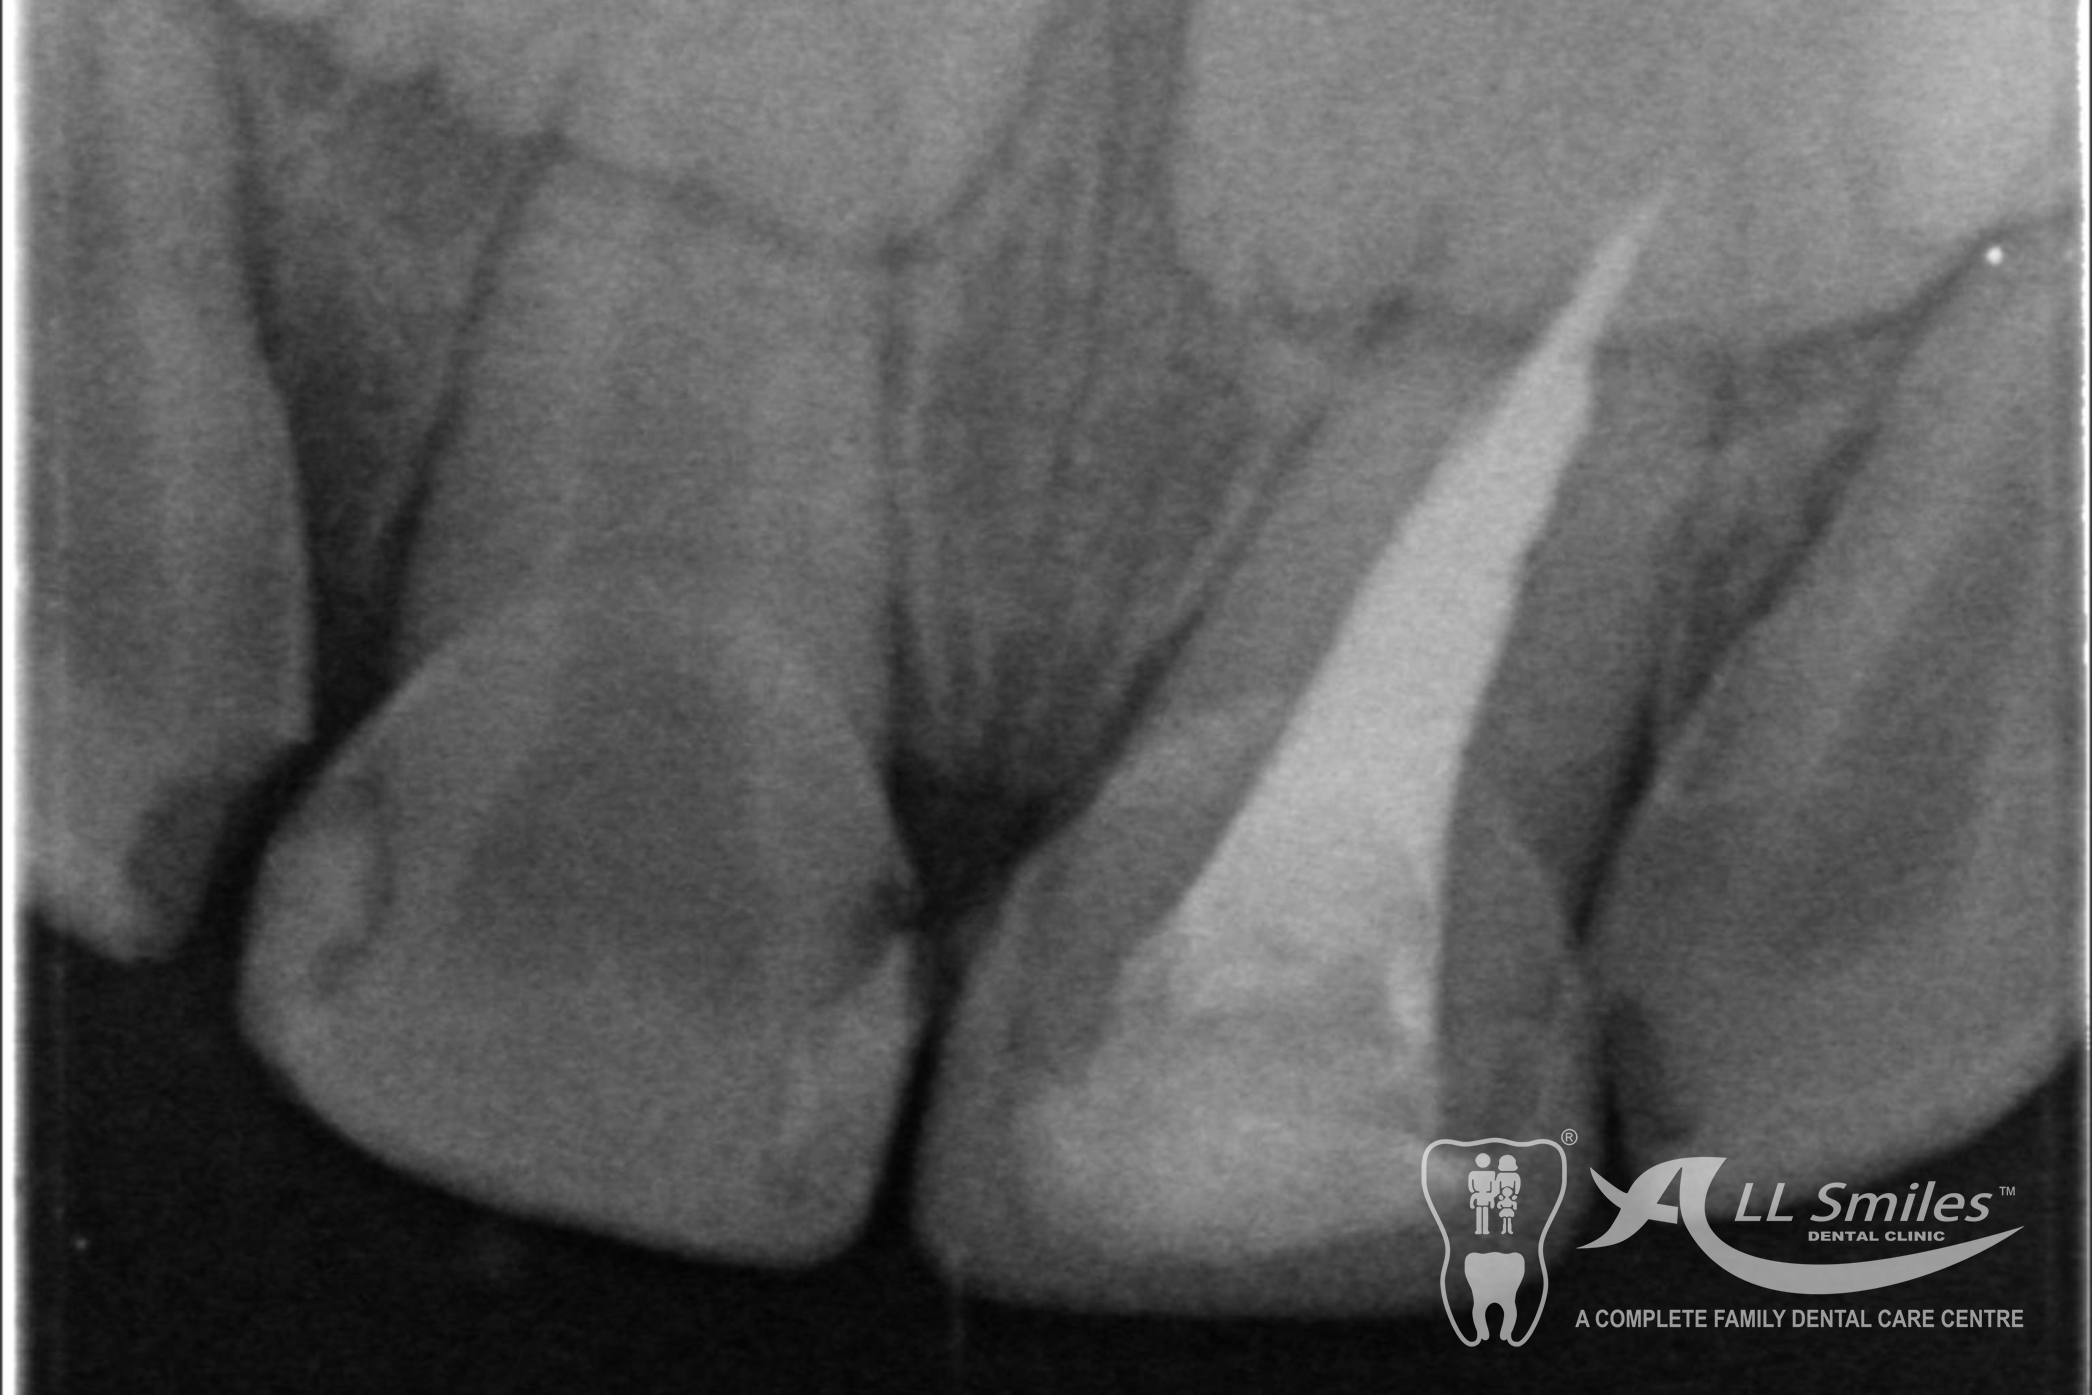

Root Canal Gallery